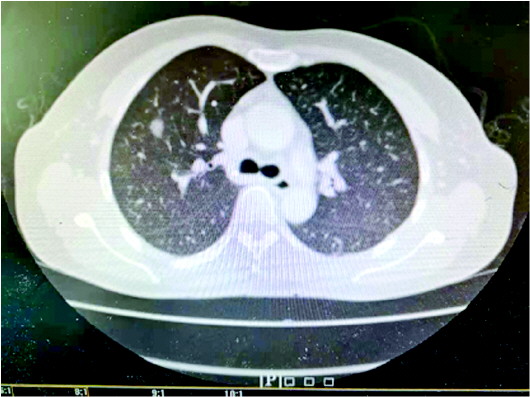

28岁的雷某近1个多月总是感觉口渴,于是猛喝奶茶、凉茶、可乐等饮料,可乐一天能喝1.5升,然而口渴症状未见减轻体重却下降大约8斤。突然有天昏迷不醒被家属送往医院,才发现是2型糖尿病酮症酸中毒,合并急性肾衰竭、急性心力衰竭、肺部感染、急性呼吸衰竭等多个脏器功能衰竭。